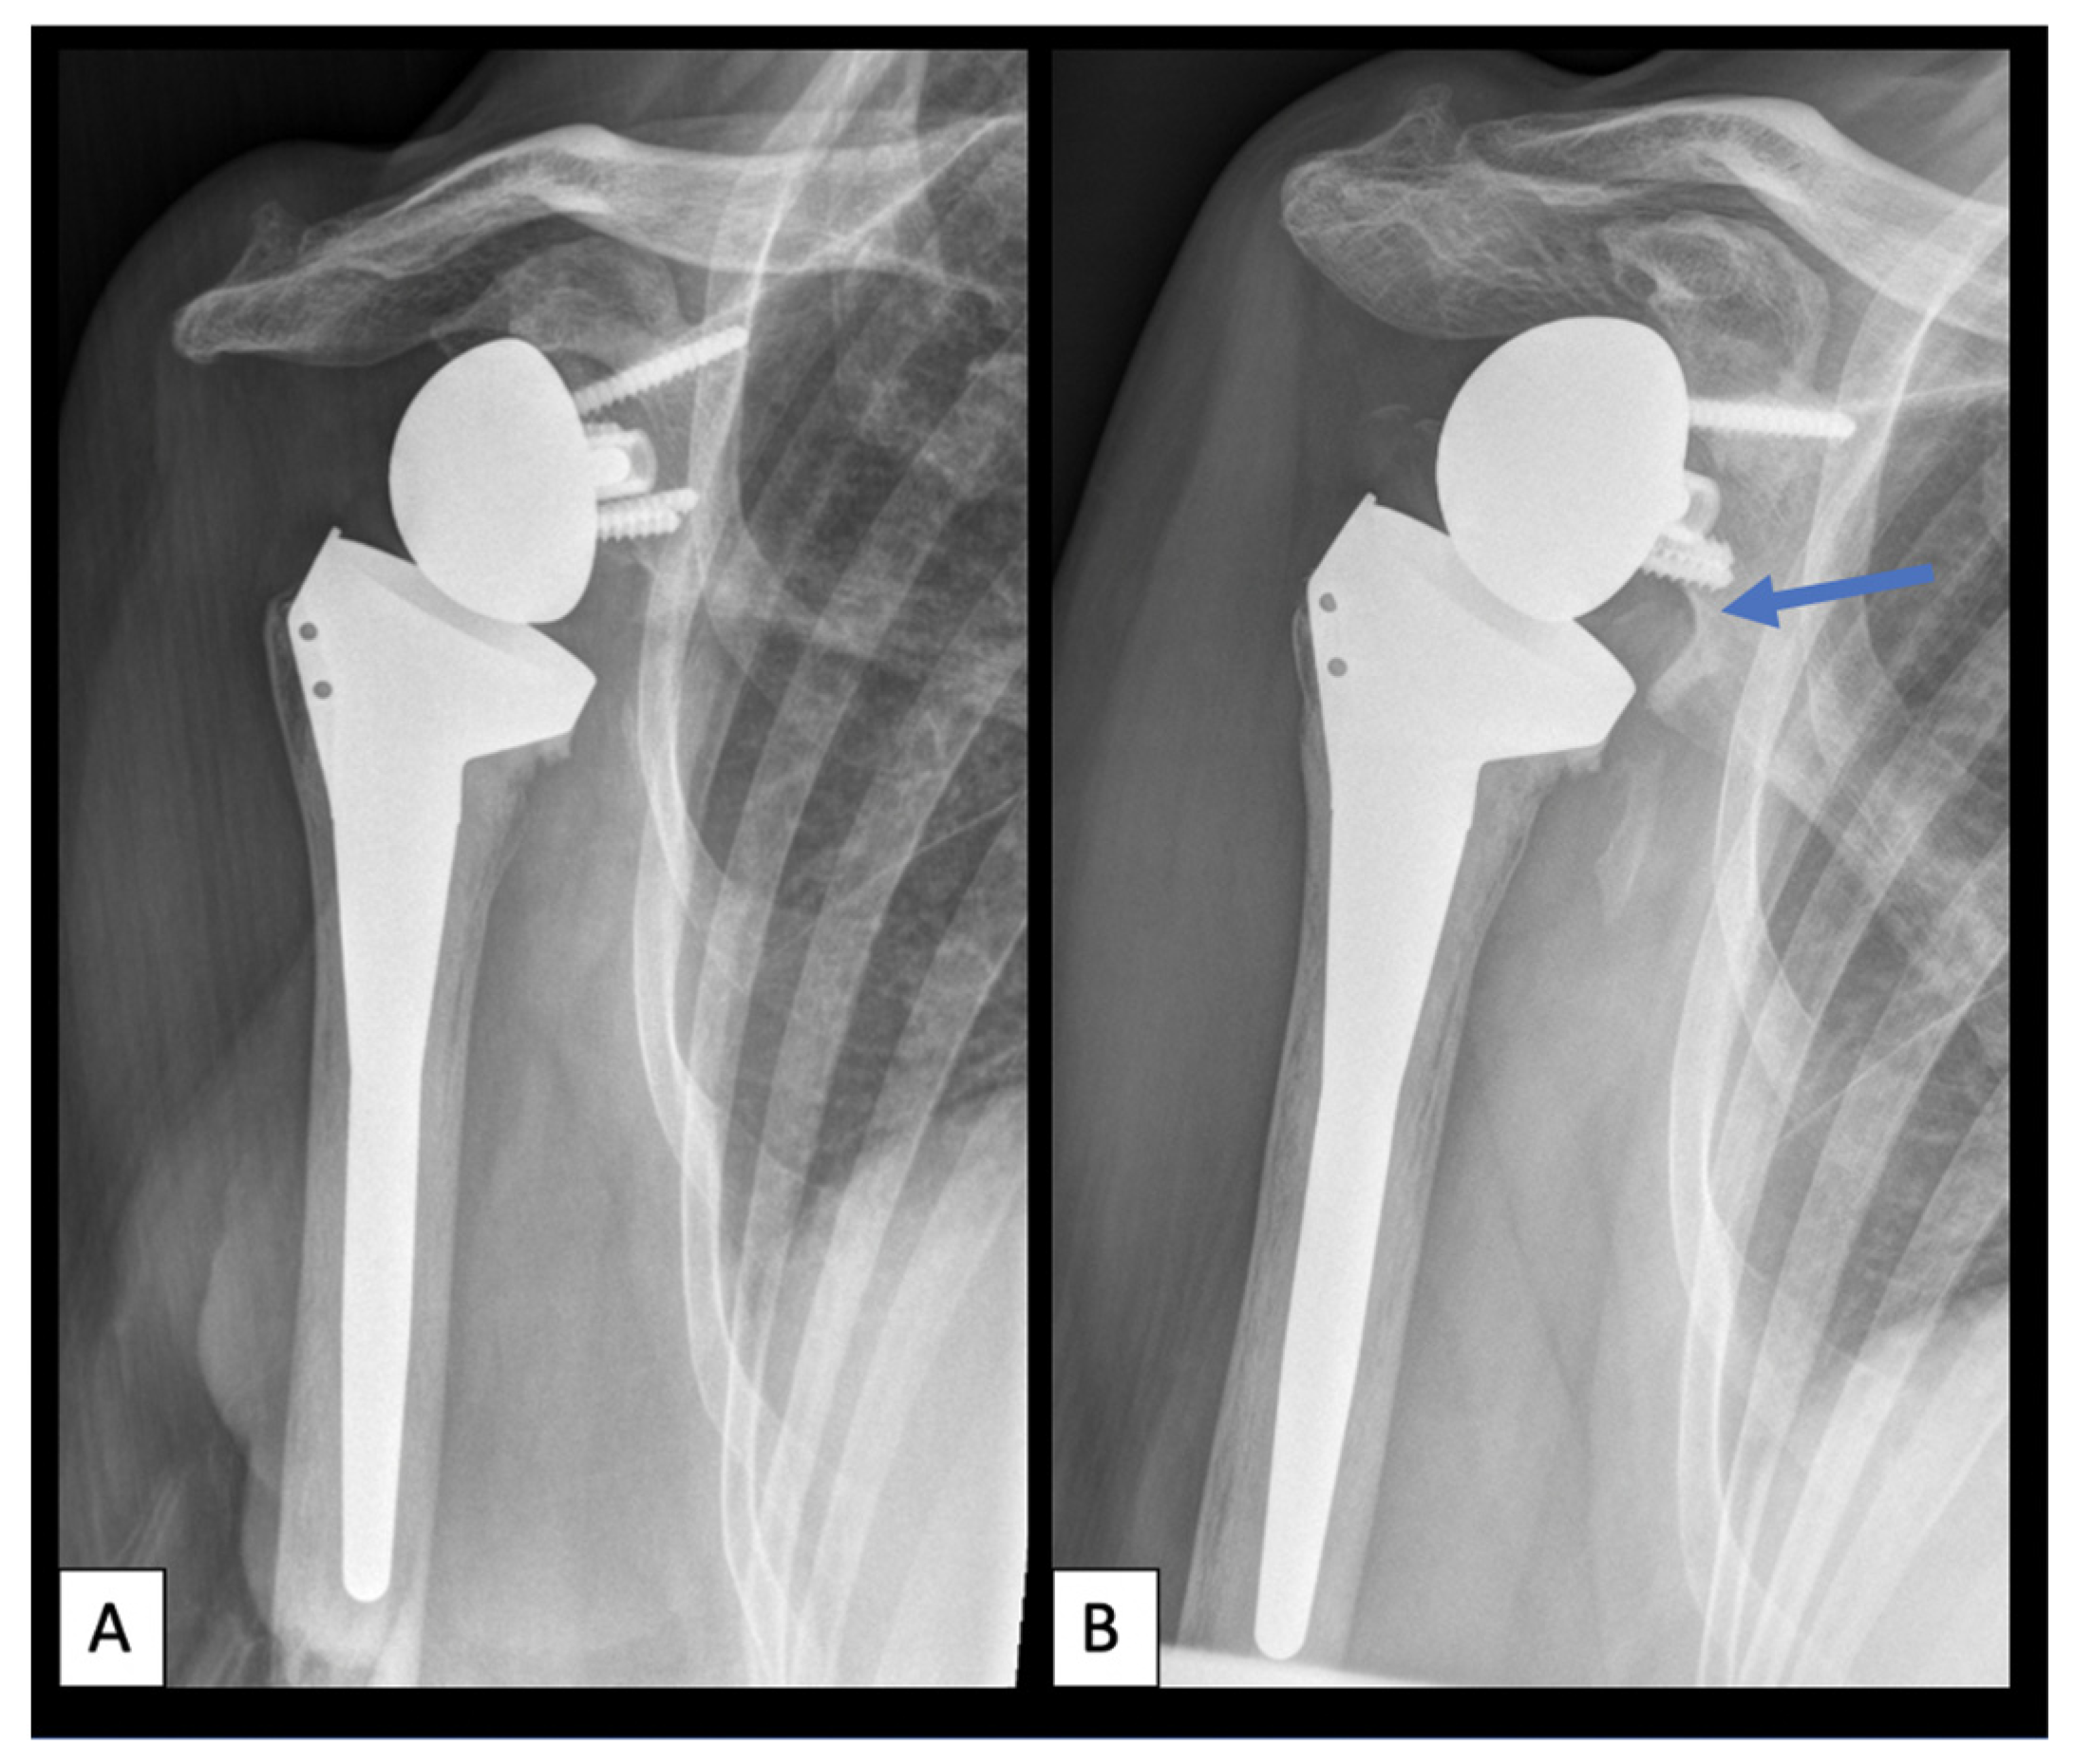

7.3. Radiographic Outcome

| Stem loosening, n (%) | 3 (13.6) |

| Glenoid loosening, n (%) | 2 (9.1) |

| Polyethylene wear, n (%) | 4 (18.2) |

| Scapular notching, n (%) | |

| Grade 1 | 3 (20%) |

| Grade 2 | 7 (46.7%) |

| Grade 3 | 5 (33.3%) |